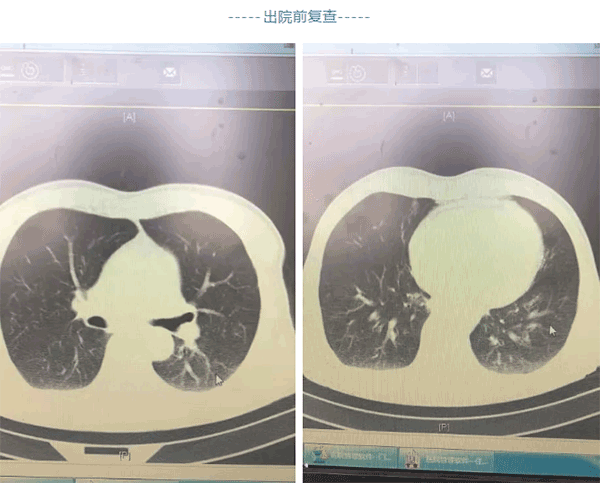

出院前复查颅脑胸部CT示积液和肺不张胸腔积液恢复良好,患者可以正常行走,现已经顺利出院。